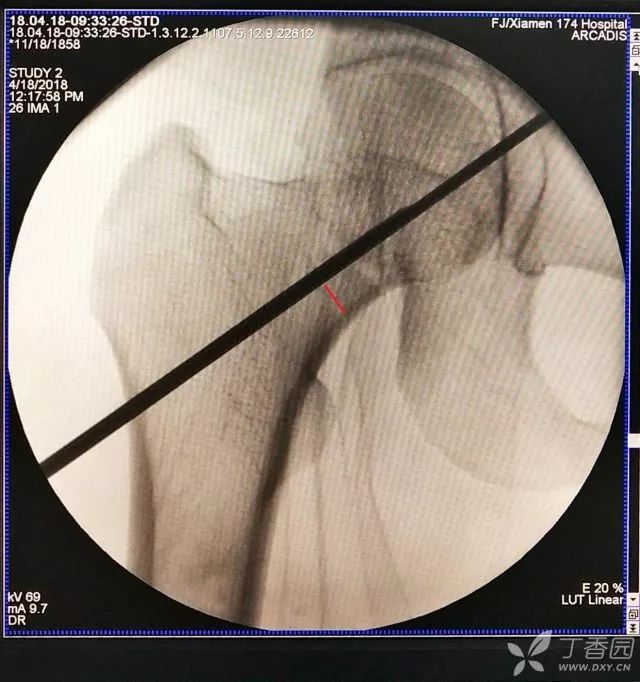

2. 倒数第二次的复位仍是欠缺一点

3. 再努力一把就基本成了

复位的关键是术前详细读片,逆受伤过程复位。这个病人主要是内旋髋关节,大体复位后就是局部微调,这个需要耐心。

闭合复位建议穿铅衣操作,但是谁也不能保证能解剖复位,如果复位不满意,必须切开,这一点不能将就。